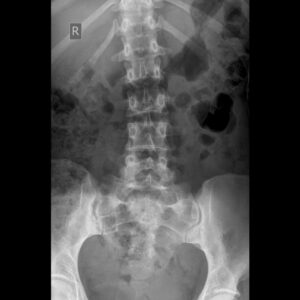

x-ray of someone's spine